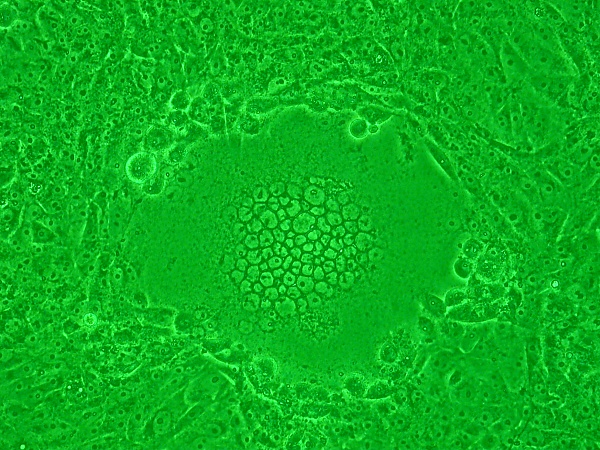

Синцитий также может образовываться, когда клетки инфицированы определёнными типами вирусов, в частности, ВПГ-1, ВИЧ, МэВ, SARS-CoV-2 и пневмовирусами, например, респираторно-синцитиальным вирусом (RSV). Эти синцитиальные образования создают характерные цитопатические эффекты, когда наблюдаются в пермиссивных клетках. Поскольку многие клетки сливаются вместе, синцитии также известны как многоядерные клетки, гигантские клетки или поликариоциты[10]. Во время инфекции вирусные слитые белки, используемые вирусом для проникновения в клетку, транспортируются на поверхность клетки, где они могут вызвать слияние мембраны клетки-хозяина с соседними клетками.

Мутации в вариантах SARS-CoV-2 содержат варианты спайковых белков, которые могут усиливать образование синцития[17]. Протеаза TMPRSS2 необходима для образования синцития[18]. Синцития может позволить вирусу распространяться непосредственно на другие клетки, защищенные от нейтрализующих антител и других компонентов иммунной системы[17]. Образование синцития в клетках может быть патологическим для тканей[17].

«Тяжелые случаи COVID-19 связаны с обширным повреждением легких и наличием инфицированных многоядерных синцитиальных пневмоцитов. Вирусные и клеточные механизмы, регулирующие образование этих синцитий, недостаточно изучены»[19], но мембранный холестерин представляется необходимым[20][21].